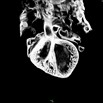

Caption Play Movie2D serial EFIC images of mutant 251-005-1 (E18.5) in the coronal view reveals overriding aorta, perimembranous VSD (pmVSD), muscular VSD (mVSD), dysplastic aortic valve, and hypoplastic transvese aorta